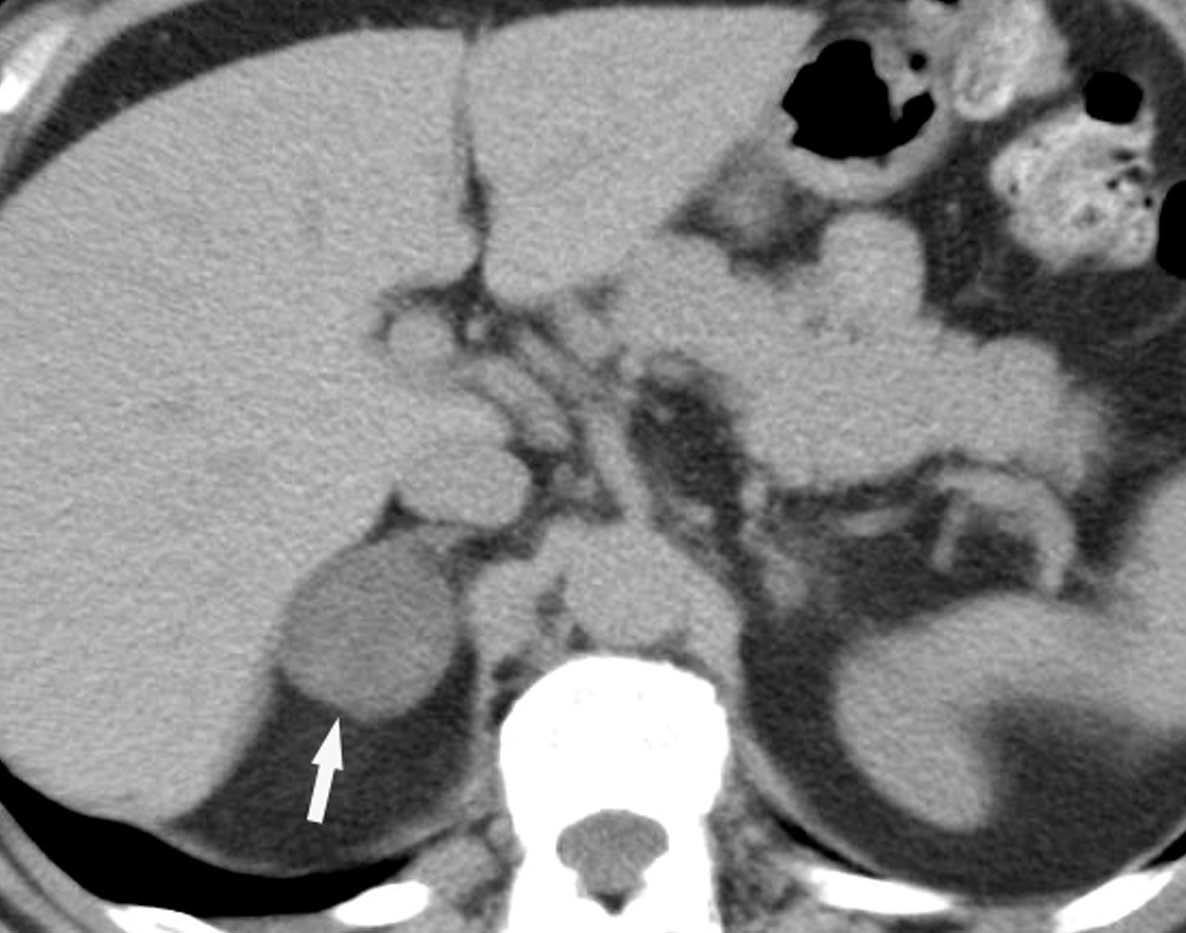

La aparición de nódulos suprarrenales se da en más del 10% de los pacientes con cáncer de pulmón. Dada la elevada frecuencia de adenomas benignos, es crucial la distinción entre éstos y la afectación metastásica. Ésta se puede llevar a cabo con una combinación de estrategias de imagen que incluyen TC, RM y/o PET. Por TC los adenomas suprarrenales típicamente tienen valores de atenuación bajos por la presencia de cúmulos lipídicos. Una lesión suprarrenal con valores de atenuación menores de 10 unidades Hounsfield (UH) en el estudio sin contraste, tiene una probabilidad del 98% de que se trate de una lesión benigna. Dado que ambas lesiones, adenomas y metástasis captan contraste, la valoración rutinaria de la captación no es útil en la diferenciación entre benignidad y malignidad. Si se detecta durante la realización de la TC, realizar cortes tardíos a los 15 minutos de la administración de contraste es importante, ya que si existe un lavado del contraste de más del 50% el diagnóstico de adenoma tiene una sensibilidad del 98% y una especificidad que oscila entre el 92 y el 100%20. La RM con secuencias de desplazamiento químico en la valoración de nódulos suprarrenales tiene una especificidad del 100% para el diagnóstico de adenoma (fig. 14). Sin embargo, la sensibilidad depende de la densidad de la lesión en el estudio con TC, ya que cuanto mayor es la densidad en la TC menos señal perderá en la RM, con lo que resulta más difícil etiquetarlo como adenoma21. La PET presenta una sensibilidad alta en la detección de metástasis suprarrenales, ya que cuando una lesión suprarrenal no muestra signos concluyentes en la TC de benignidad, la ausencia de actividad con la PET hace muy probable dicho diagnóstico. En los casos en que persistan dudas diagnósticas se debe recurrir a la biopsia de la lesión adrenal, especialmente si de este diagnóstico depende el manejo del paciente.

Metástasis hepáticas y suprarrenales